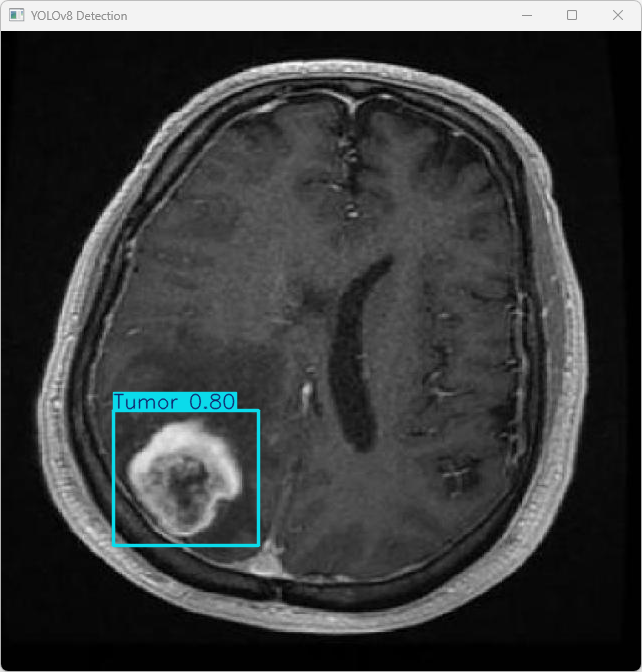

执行imgTest.py代码后,会将执行的结果直接标注在图片上,结果如下:

该输出基于YOLOv8模型对数字图像文件imagetest.jpg进行检测所得

图像信息:

(1)处理的图像路径为:TestFiles/imagetest.jpg。

(2)图像尺寸为640×640像素。

检测结果:

(1)模型在图片中检测到:1 个肿瘤 (Tumor)。

处理速度:

(1)预处理时间: 6.1 毫秒

(2)推理时间: 5.0 毫秒

(3)后处理时间: 102.6 毫秒

该系统基于YOLOv8模型,在医学影像脑肿瘤检测方面已获得较高水平的能力,并可用于将其应用于实际临床诊断场景。